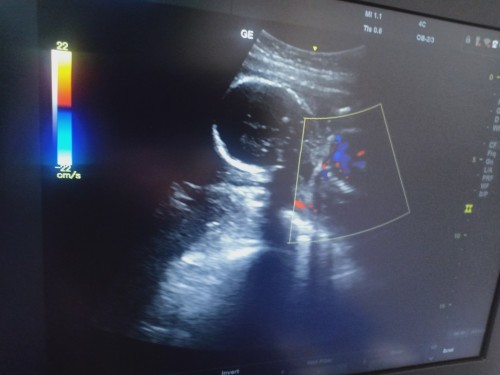

20week มองยังมั้ยเป็นเรย